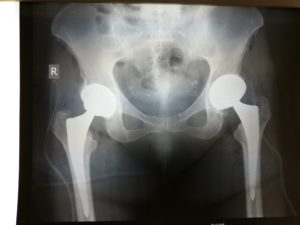

Περίπτωση ταυτόχρονης αρθροπλαστικής AMIS για αμφοτερόπλευρη οστεοαρθρίτιδα Ισχίου

Η καλή κατάσταση γενικής υγείας επέτρεψε να γίνει ταυτόχρονη, σε μια επέμβαση, αρθροπλαστική Ισχίου.

Ο ατραυματικός και συγκριτικά αναίμακτος χαρακτήρας της AMIS είχε ως αποτέλεσμα την άμεση κινητοποίηση της ασθενούς. Λίγες ώρες μετά την επέμβαση ταυτόχρονης AMIS η ασθενής βάδισε με τη βοήθεια περιπατητήρα.

Την επόμενη μέρα βαδίζει αυτόνομα και πρακτικά είναι έτοιμη να επιστρέψει σπίτι της.

Δύο εβδομάδες μετά την επέμβαση η ασθενής είναι πολύ ευχαριστημένη, κινείται αυτόνομα και είναι ιδιαίτερα ικανοποιημένη από το γεγονός ότι δε θα χρειαστεί να επιστρέψει στο χειρουργείο για μια δεύτερη επέμβαση για την αρθρίτιδα που την ταλαιπωρούσε.